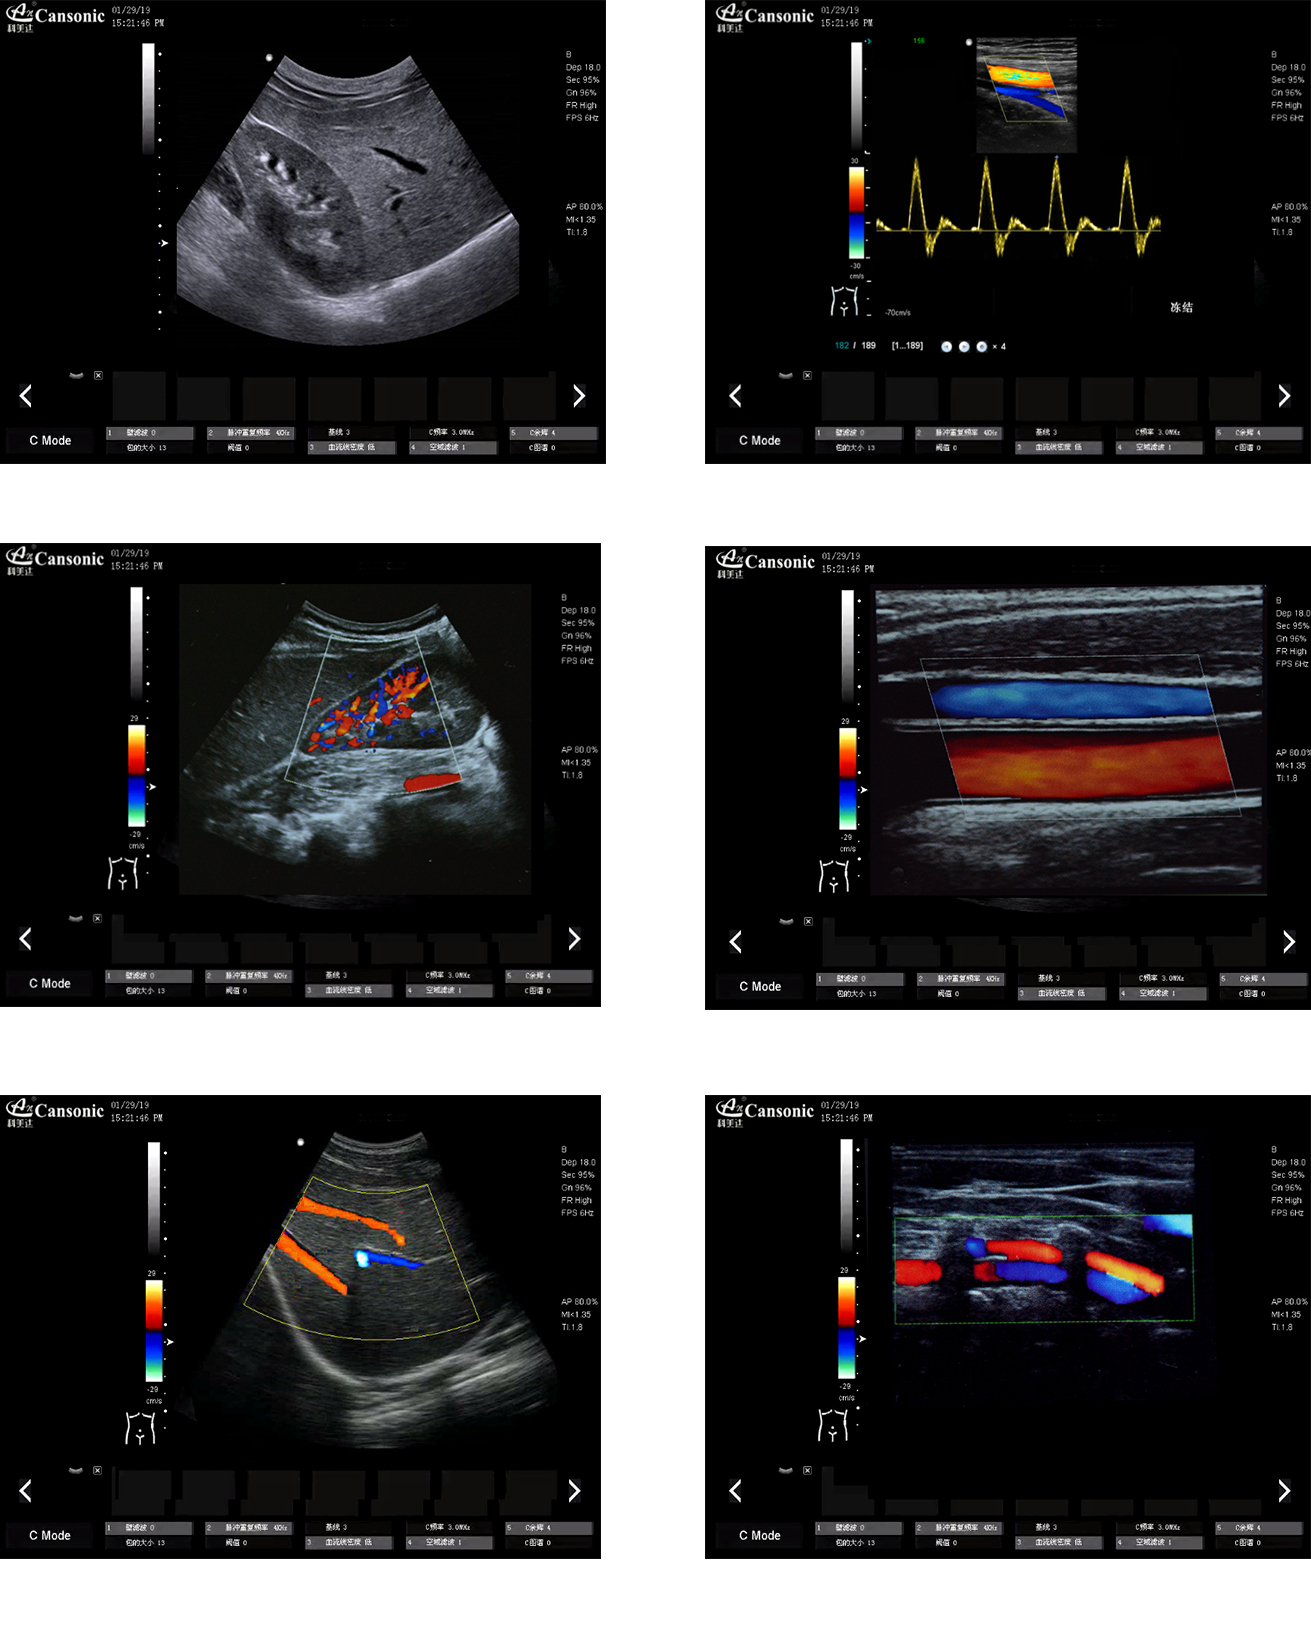

科美達(dá)K22圖像實例